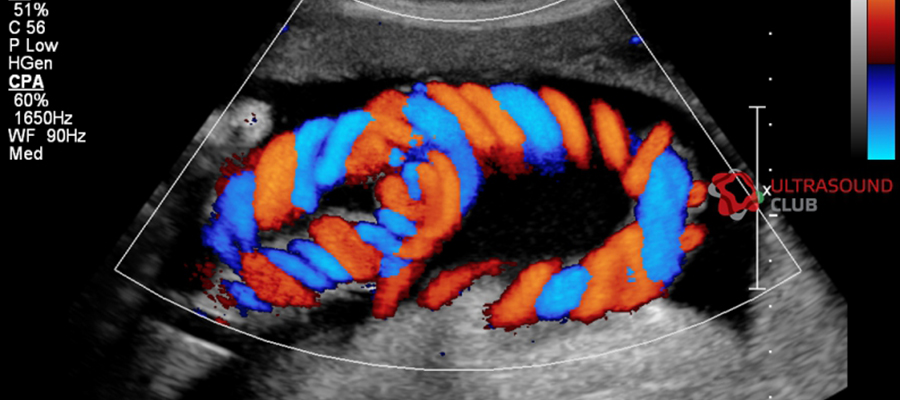

Renkli doppler ultrasonografi çekimi için hastanın özel bir hazırlık yapmasına gerek yoktur.  Genellikle doktor muayenehanelerinde de bulunan cihaz görüntüleme merkezleri ve özel hastanelerde devlet hastanelerinde yapılmaktadır.  Jel sürülerek normal ultrasonografi çekimi gibi gerçekleşir.  Ancak renkli doppler ultrasonografi görüntüde özellikle kan damarları kırmızı olarak görüntülenir.  Kırmızı rengin dışında mavi renk aradaki kontrastı oluşturmak için kullanılır.  Mavi ve kırmızı renkler öncelikle renkli doppler ultrasonografi de görünen renklerdir.  Ciddi anlamda damarlarla ilgili tanı koymaya yardımcı en önemli tetkik cihazlarından biridir.

Renkli Doppler Ultrasonografi

Renkli doppler kan damarlarının tamamını ve kan akışını ekrana görüntü olarak yansıtır.  Aynı zamanda bilgisayar ekranına kan damarlarının görüntüsünü ve afişlerini renkli olarak aktarır.  Ultrasonografide iki renk kullanılır.  Mavi ve kırmızı renk haritasıyla kan akışının hareketini görsel olarak aktarır.  Mavi renk genellikle sabit bölgeyi gösterir,  kırmızı renk ise kan akışının hızını ve yerini tespit eder.

Renkli Dopplerin Özellikleri

Renkli doppler ultrasonografi de kan damarlarının akışının genel olarak görüntüsünü ekrana yansıtılır.  Çözünürlüğü oldukça düşüktür.  Bu nedenle sınırlı akış bilgisi sağlar.  Ancak renkli akış haritası çıkardığı için çok faydalı tetkiklerden biridir.  Yön akış bilgisini verir.  Aynı zamanda hız bilgisi ile birlikte türbülanslı akışına da gösterir. Renkli Doppler Ultrasonografi Fiyatları 2026 için bizimle iletişime geçiniz.